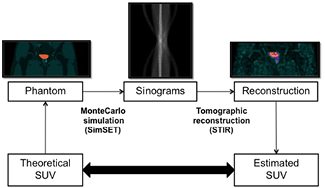

Both geometric and anthropomorphic physical phantoms have been widely used for investigating the impact of different factors on the output PET images, enabling for us applications that cannot be performed with patient studies. Nevertheless, they have several important limitations, such as reduced flexibility for changing shapes and volumes of the internal structures, high cost, and cumbersome use. An alternative is the use of digital phantoms (Zaidi and Xu 2009), so that simulated PET studies can be generated from the realistic projection of digital phantoms by using computer simulation techniques. In this work, we generated a database of 18F-FCH PET studies by Monte Carlo (MC) simulation of a modified version of the XCAT2 phantom (Extended Cardiac-Torso Phantom Version 2.0) (Segars et al 2010). Figure 2 shows a general layout of the experiment, which allowed us to investigate the impact of bladder uptake on prostate SUV values in a realistic and well-controlled framework.

Figure 2. General layout of the simulation experiment.

This approach is inspired by the methodology to correct physiological background radioactivity on dynamic acquisitions originally proposed by Tsoumpas and Thielemans (2009). A schematic layout of the process can be observed on figure 3.

Figure 3. Layout of the correction method process. The original sinograms are reconstructed using STIR. Afterwards, the bladder is segmented and then projected using the STIR analytical projector used inside the reconstruction. Finally, the image is reconstructed again using the obtained sinograms as a background term, obtaining the corrected images without the bladder contribution.